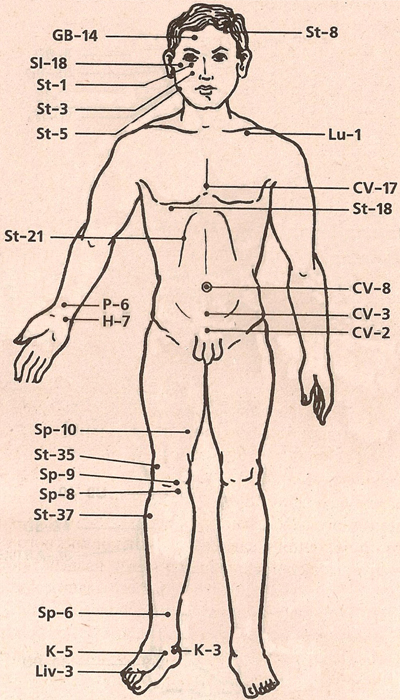

Исцеляющие точки нашего организма.

подробный атлас

Исцеляющие точки нашего организма.

подробный атлас

АКУПУНКТУРНЫЕ ТОЧКИ

АКУПУНКТУРНЫЕ ТОЧКИ

АКУПУНКТУРНЫЕ ТОЧКИ ПРИ ЛЕЧЕНИИ МАГНИТАМИ